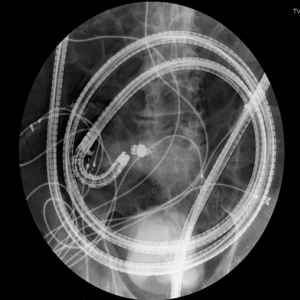

以前小腸は「暗黒大陸」といわれた時期があるほど、なかなか有効な検査がありませんでした。2001年よりカプセル内視鏡、バルーン内視鏡という小腸粘膜を直接観察できる検査が登場したことにより、小腸領域の診断・治療はめざましく発展しております。

当院では2009年にカプセル内視鏡、2010年にバルーン内視鏡を導入いたしました。

カプセル内視鏡は26mm×11mmの小さいカプセル状の内視鏡の機械を飲み込んで、消化管内を撮影していく検査法です。カプセルが胃腸の動きに合わせて腸管内を移動していき、その間1秒間に2枚ずつ写真を撮影していきます。最後にその写真をコンピュータで編集し、1本の動画にして、内視鏡医が観察、診断します。カプセル内視鏡の利点は、簡便性です。患者さまへの身体的な苦痛はほとんどないため、小腸のスクリーニング検査として最適です。2011年よりすべての小腸疾患が疑われる症例に対して検査が行えるようになったため、ますます身近な検査となっていくことと思います。

当院では現在まで約200例のカプセル検査を実施しており、多くの症例の診断に貢献してきました。このような経験を反映し、今年度よりカプセル内視鏡学会指導施設に承認される予定です。

小腸潰瘍

一方でバルーン内視鏡検査は、約5mある小腸粘膜を直接観察することができます。カプセル内視鏡と比較して苦痛を伴う検査となりますが、組織生検や内視鏡治療が実施できることが利点です。現在当院では約100例のバルーン内視鏡検査を行ってきました。実際行った治療としては、小腸がんや小腸ポリープの内視鏡的切除、小腸出血に対しての内視鏡的止血術、小腸が狭くなって便が通らなくなった患者に対して、内視鏡的バルーン拡張術などがあります。